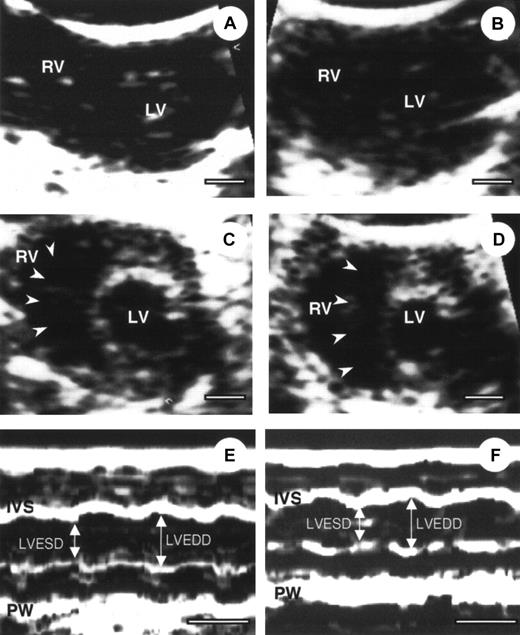

To define the cardiac condition after AMI, α2-AP−/− and α2-AP+/+ mice were subjected to echocardiography.25 Four representative echocardiograms from pre- and post-AMI of α2-AP−/− and α2-AP+/+ mice are shown in Figure2. No difference between cardiac function was seen in α2-AP−/− and α2-AP+/+ mice before coronary ligation (Figure 2A,C). After coronary ligation, a global decrease in cardiac function was observed in both types of mice without a marked change of cross-sectional area of the LV. However, in α2-AP−/− mice, the cavity of the RV was markedly dilated after coronary ligation (Figure 2D), in contrast to α2-AP+/+ mice (Figure 2B). Also the cross-sectional area of the RV in α2-AP−/− mice (9.4 ± 1.2 mm2) was markedly increased compared with that in α2-AP+/+ mice (2.5 ± 0.4 mm2). This finding indicated that the RV function was greatly affected by some kind of stress after AMI in α2-AP−/− mice. However, the findings using M-mode echocardiograms clearly show alteration of the LV function after ligation in α2-AP−/− mice (Figure 2E,F). Before coronary ligation, LVEDD and LVESD were 2.5 ± 0.2 mm and 1.5 ± 0.1 mm, respectively (Figure 2). LVEDD decreased to 2.3 ± 0.2 mm, but LVESD did not change (1.5 ± 0.2 mm) after coronary ligation. In α2-AP−/− mice, the calculated FS (40.0% ± 1.5%) before ligation slightly decreased to 34.8% ± 2.2% after ligation (Figure 2E,F). In wild-type mice, the calculated FS was not markedly different from that of α2-AP−/− mice (data not shown).

Echocardiography of α2-AP+/+ and α2-AP−/−mice.

Representative example of 2-dimensional echocardiography (A-D) and M-mode echocardiograms (E,F) from α2-AP+/+ (A, before coronary ligation; B, after coronary ligation) and α2-AP−/− mice (C,E, before coronary ligation; D,F, after coronary ligation). M-mode echocardiograms showed the change of LVEDD after ligation in α2-AP−/− mice. White bar represents 1 mm (A-D) or 100 ms (E,F). Note, interventricular septum (arrowheads) deviated to left side after coronary ligation; IVS, interventricular septum; PW, posterior wall.